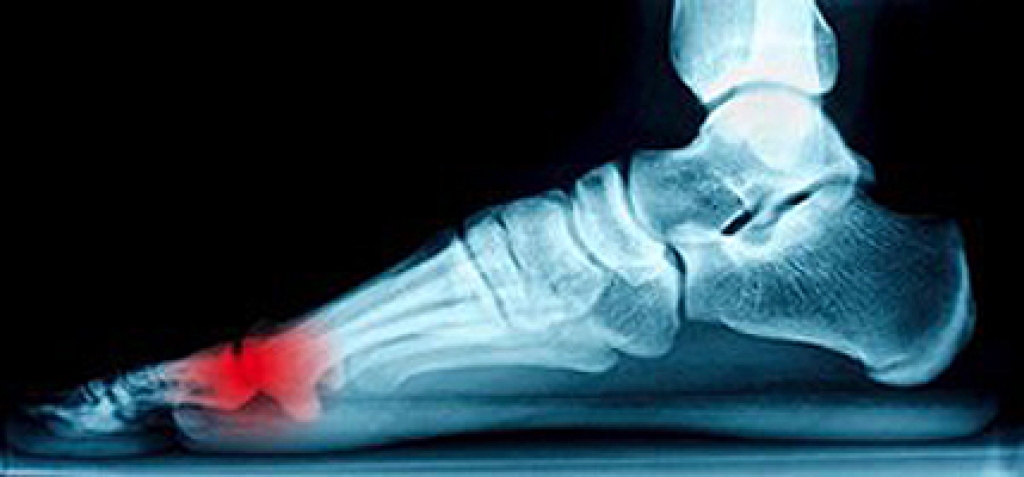

If you have broken a foot, you are aware of the severe pain that typically accompanies this condition. It may happen as a result of falling, or from enduring a sports injury. There are two different types of fractures, which are labeled as compound or closed fractures. The former represents a break in which the bone protrudes through the skin. Some of the symptoms that are associated with a broken foot may include pain in and around the affected area, in addition to possible bruising or swelling. Walking or standing may be painful, and many patients use crutches to increase mobility. After a proper diagnosis is performed, which typically includes having an X-ray taken, correct treatment can begin. This will generally consist of wearing a cast, protective boot, or splint. If you have broken your foot, please consult with a podiatrist who can prescribe the best course of treatment for you.

A broken foot is caused by one of the bones in the foot typically breaking when bended, crushed, or stretched beyond its natural capabilities. Usually the location of the fracture indicates how the break occurred, whether it was through an object, fall, or any other type of injury.

Treatment for broken bones varies depending on the cause, severity and location. Some will require the use of splints, casts or crutches while others could even involve surgery to repair the broken bones. Personal care includes the use of ice and keeping the foot stabilized and elevated.